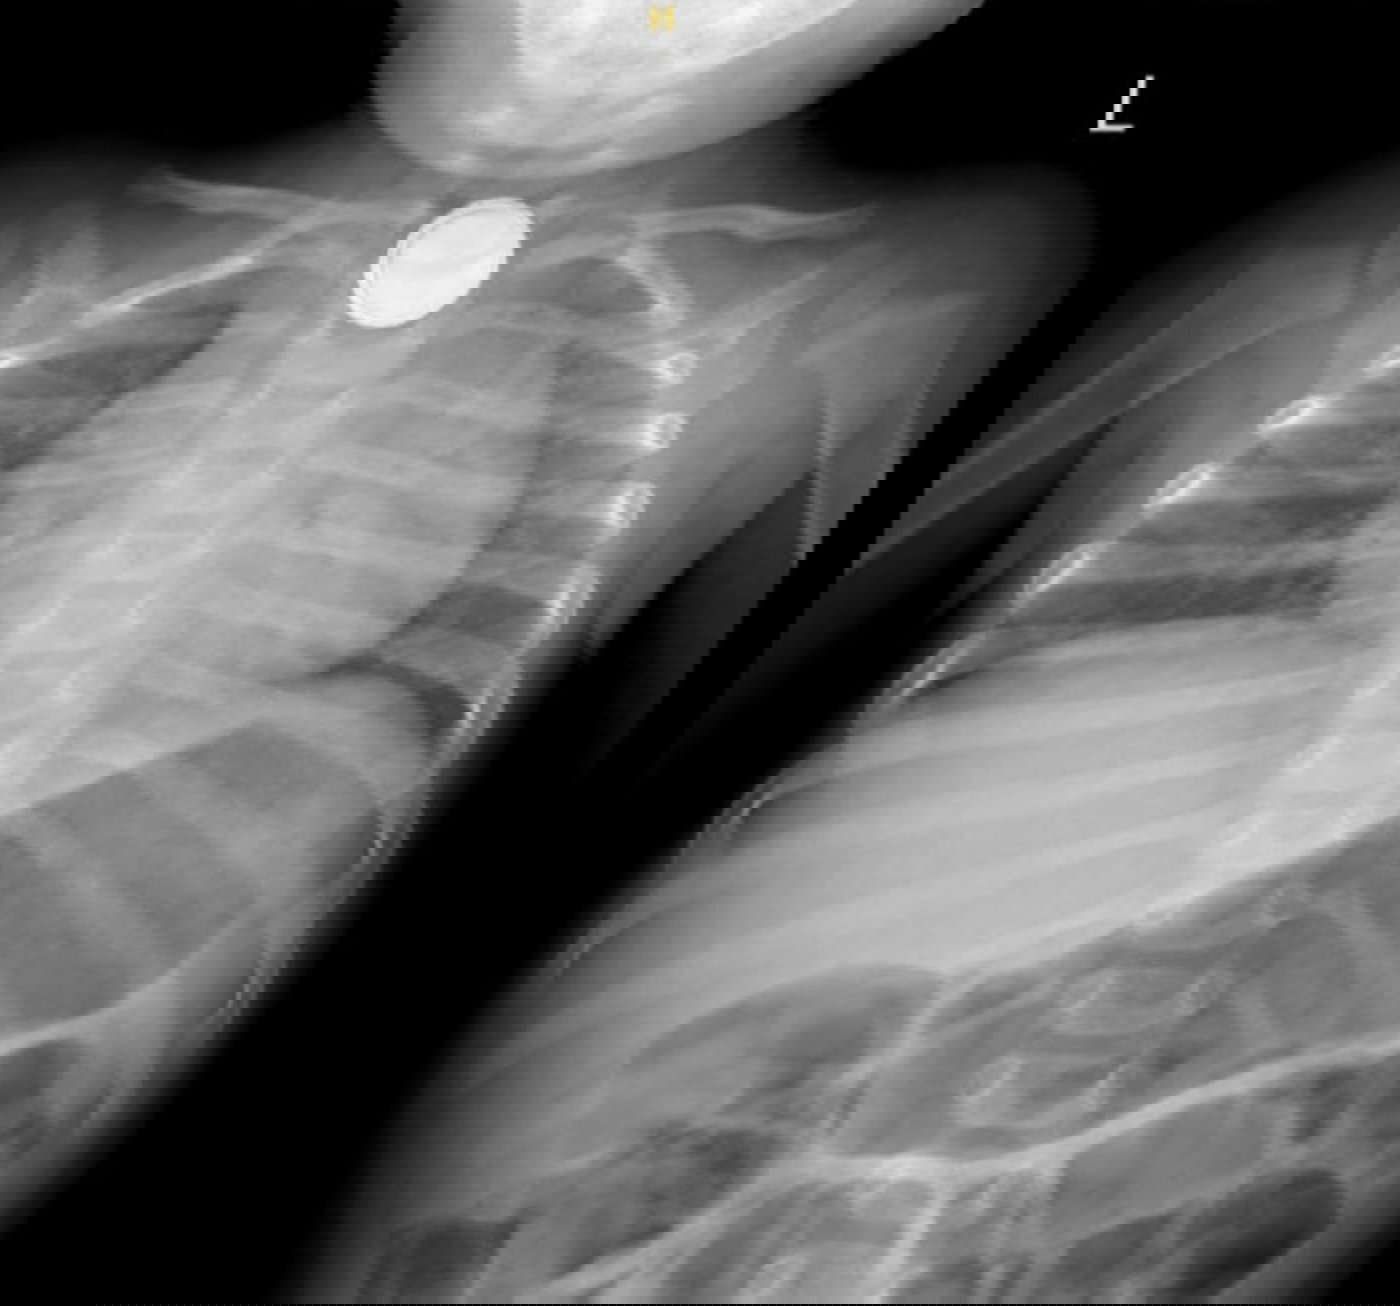

ד"ר דניאל כהנא, מתמחה ברפואת ילדים, קיבלה את הפעוט במלר"ד הילדים וזיהתה במהירות את חומרת המצב. בצילום רנטגן אובחנה הסוללה בוושט העליון, ממצא שהצריך טיפול דחוף. בתוך זמן קצר הוזעק צוות גסטרו ילדים, ניתן טיפול ראשוני בדבש – טיפול ייעודי למקרים של בליעת סוללה למניעת נזק לרקמה – והפעוט הועבר באופן מיידי לחדר ניתוח.